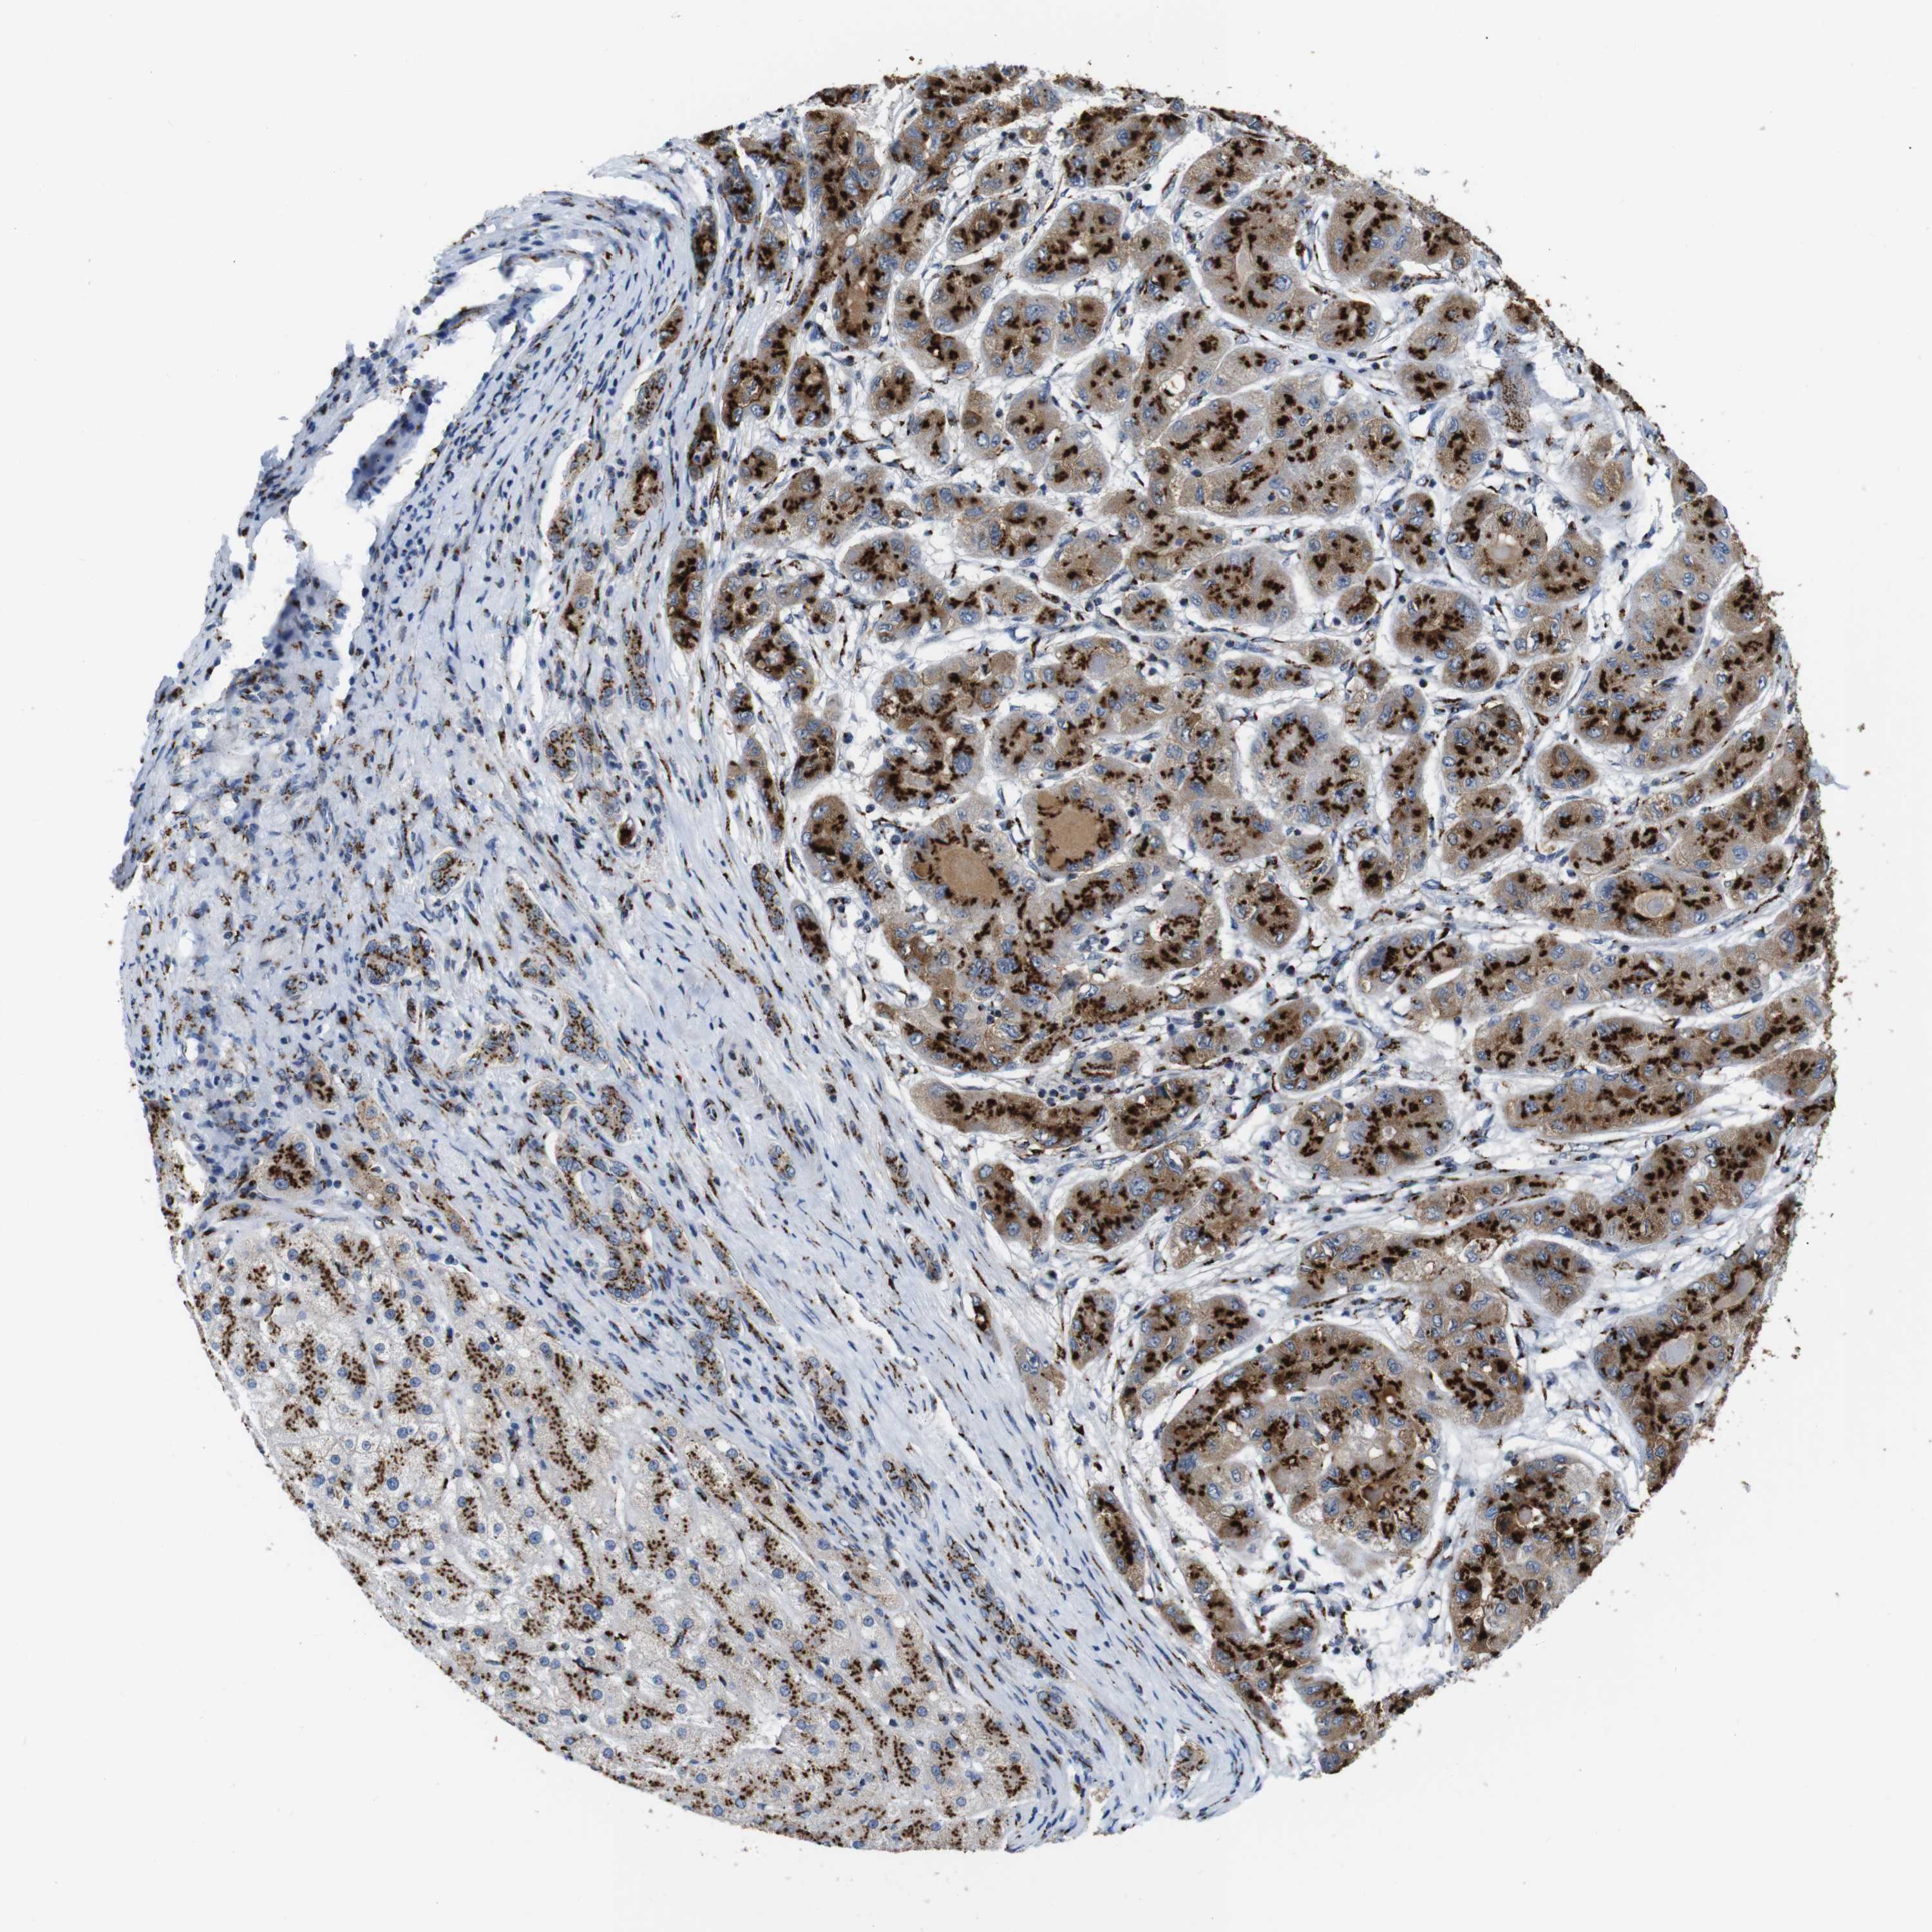

LIVER CANCER - Protein expressioni

A mouse-over function shows sample information and annotation data. Click on an image to view it in a full screen mode. Samples can be filtered based on level of antibody staining by selecting one or several of the following categories: high, medium, low and not detected. The assay and annotation is described here.

Antibody stainingi

Antibody staining in the annotated cell types in the current human tissue is reported as not detected, low, medium, or high, based on conventional immunohistochemistry profiling in selected tissues. This score is based on the combination of the staining intensity and fraction of stained cells.

Each image is clickable and will lead to virtual microscopy that enables deeper exploration of all samples and also displays staining intensity scores, fraction scores and subcellular localization as well as patient and tissue information for each sample.

Antibody HPA012609

Antibody HPA012723

Antibody CAB011489

Staining

High

Medium

Low

Not detected

Intensity

Strong

Moderate

Weak

Negative

Quantity

>75%

75%-25%

<25%

None

Location

Nuclear

Cytoplasmic/membranous

Cytoplasmic/membranous,nuclear

Cholangiocarcinoma

Carcinoma, Hepatocellular, NOS